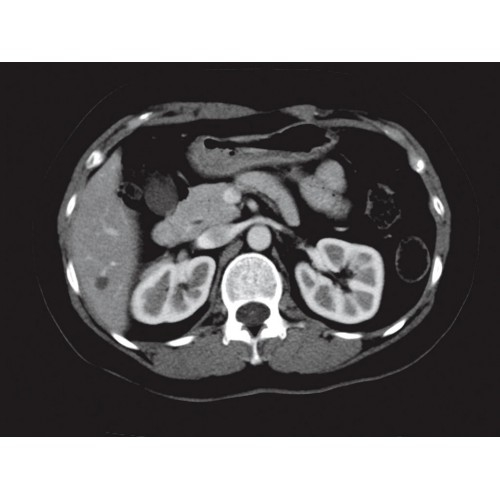

Позволяет проводить комплексные исследования всех анатомических зон, включая нейровизуализацию, ангиографию, исследования органов грудной и брюшной полости. Особенно эффективен для раннего выявления онкологических заболеваний.

Специализированные исследования